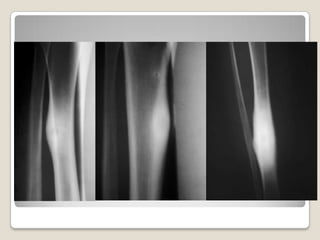

Rx

En Rx el tumor se aprecia

como una zona

radiotransparente redonda

y pequeña mineralizada

en el centro NIDO

Rx  En Rx eltumor se aprecia como una zona radiotransparente redonda y pequeña mineralizada en el centro NIDO